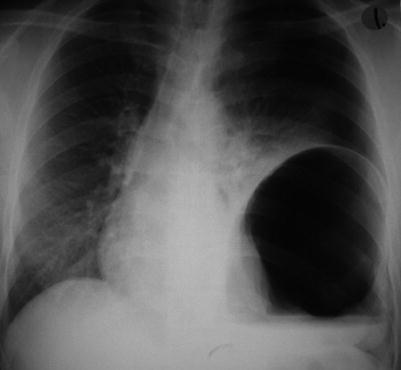

Fig. 39.2

Air-filled stomach incarcerated in the chest